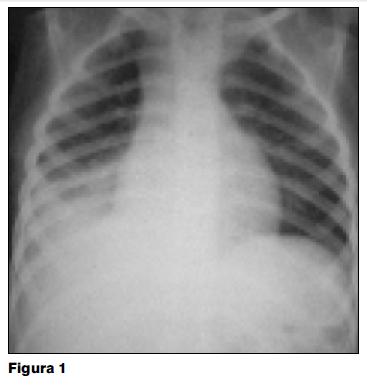

La radiografía de tórax al ingreso (figura 1) muestra diferencia volumétrica pulmonar, con pulmón izquierdo de mayor volumen y herniado contralateralmente (pulmonocele). El pulmón derecho presenta volumen reducido. Desplazamiento mediastinal hacia la derecha. En tercio inferior del pulmón derecho se superponen dos opacidades. Una compatible con atelectasia de segmentos basales del lóbulo inferior y otra opacidad de tipo parenquimatoso con aspecto de neumonía. Recibe ampicilina intravenosa durante 10 días. Durante toda la evolución en el hospital de Durazno presenta fatiga, tos nocturna y picos febriles aislados. Se otorga el alta a los 15 días de ingreso con una mejoría parcial, persistiendo con tos y fiebre ocasional.